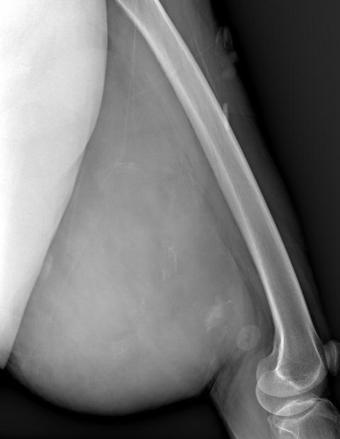

Mardin’de yaşayan H.T. (42), 3 yıl önce sağ baldırının arka kısmında oluşan ve başlangıçta yumurta büyüklüğünde olan kitlenin zamanla büyümesi üzerine Dicle Üniversitesi Tıp Fakültesi Hastanesi Ortopedi ve Travmatoloji Bölümü’ne başvurdu. Muayenede yumuşak doku kitlesi olduğu değerlendirilen şişliğin alınması için Ortopedi ve Travmatoloji Anabilim Dalı Öğretim Üyesi Prof. Dr. Emin Özkul ve ekibi tarafından ameliyat kararı verildi. Yaklaşık 2 saat süren operasyonla kitlenin çıkarıldığı, kitlenin 5 kilo 668 gram geldiği belirtildi.

Prof. Dr. Emin Özkul, vücutta görülen kitlelere büyümeden müdahale edilmesi gerektiğini ifade ederek, “Hastamız 42 yaşında bir kadın. Komşu şehir Mardin’den geldi. Bölge hastanesi olduğumuz için bu tür hastalar Mardin’den, Şırnak’tan ve diğer illerden çok geliyor. Bu hastalara önerimiz; ‘küçük bir kitle, ağrısız bir kitlem var, ele gelen bir şişliğim var ama bunda ağrı olmadığı için herhangi bir şey olmaz’ dememeli. En yakın sağlık kuruluşuna başvurup en azından kitlenin bir öneminin olup olmadığını teyit edilmesi, bir uzman tarafından bunun doğrulanmasını istiyoruz. Bu hasta da 3 yıl önce fark edilmiş küçük bir kitle, zamanla çok büyük boyutlara, yaklaşık 6 kiloya varan boyutlara varmıştı. Neredeyse bütün bacak boyu yayılan bir kitlesi mevcuttu. Bu kadar büyümenin şöyle sıkıntıları oluyor, kişinin bacağında, kolunda fonksiyon kaybına, yeri geliyor ekstremite kaybına, yani bacağını kaybetmesine yol açabilecek sıkıntılara yol açıyor. Küçükken bunlarla baş etmek daha kolay. Kişinin ekstremitesinde, bacağında, kolunda bir sıkıntı yaratmadan bunları telafi etmek, bunları alıp çıkartmak, ameliyatla bunları tedavi etmek daha kolayken bu boyutlara vardığında kişinin bacağında, kolunda fonksiyon kaybı, sakatlık riski çok yüksek oluyor. Bu sebeple küçükken önleminin alınmasında yarar var” dedi.

Kitlelerin görülmesi halinde sağlık kuruluşlarına başvurulması gerektiğini belirten Prof. Dr. Özkul, “Hastamızda yaklaşık olarak 3 yıl önce şikayetleri başlamış. Sonra zaman içerisinde hızla büyüyen bir kitleye sahipti. Şanslıydı ki herhangi bir sinirine zarar vermemişti. Hayatına fonksiyon bozukluğu olmadan devam edebilecek. Bölgemize yaşayan ve ülkemizde yaşayan herkese şunu söylüyoruz. Küçük de olsa yumuşak doku kitlelerini önemsemeleri ve uzman görüşü almalarını öneriyorum. Bu hastadan 5 kilo 668 gramlık bir kitle çıkarttık. Bu benim mesleki yaşamım boyunca çıkarttığım en büyük kitlelerden bir tanesiydi. Biraz daha büyük boyutlara varmış olsa kişinin bacağını kurtarma şansınız olmuyor. Bu sebeple bunlara dikkat etmek gerekiyor. Hızlı büyüyen bir kitleniz var ise, ağrısız da olsa mutlaka ve mutlaka tedavi için en yakın sağlık kuruluşuna veya bizim üniversitemizin polikliniklerine başvurabilirsiniz” diye konuştu.